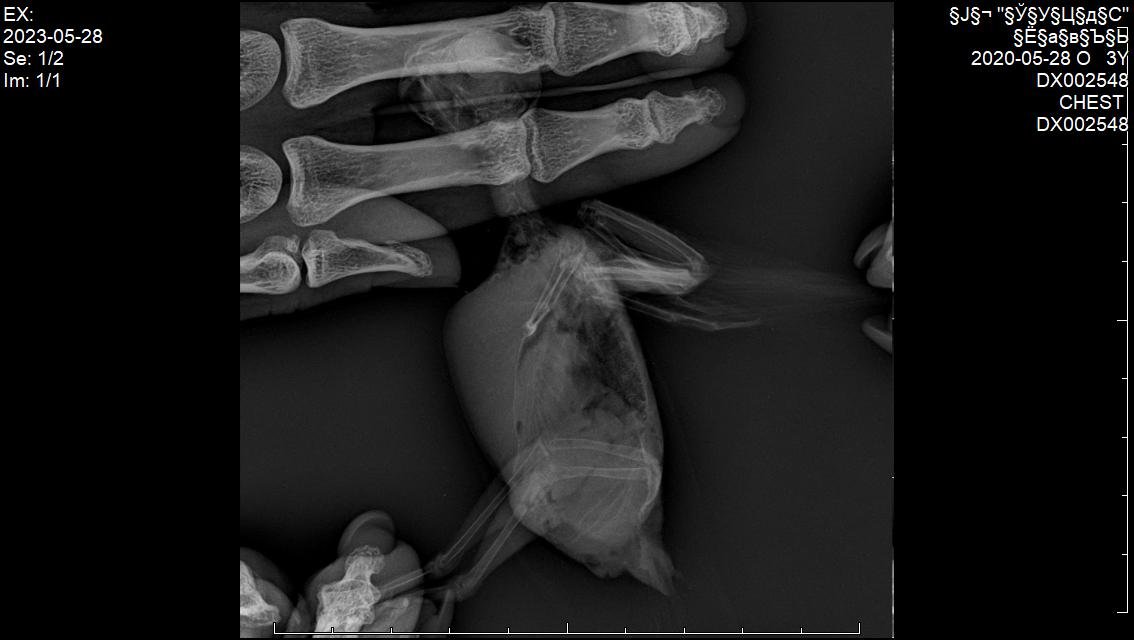

В общем, неделю назад сделали рентген (прикладываю фото). Самим сразу уже стало понятно, что дела плохи. В среду со мной связалась врач, сообщила что у нас обширная опухоль в области целома с большим давлением на органы. Случай неизлечимый.

Назначили: мелоксидил суспензию, габапентин и гептрал для паллиативного лечения.

Вот только я не поняла откуда у него эта опухоль растёт. Врач нам не сказала ни про какой-то орган, то ли это проблема с печенью, то ли семенники.

Прошу врачей форума помочь как-то более детально разобраться в наших снимках, чтобы просто в целом видеть картину и во избежании подобных ситуаций в будущем.

IMG-20230603-WA0006.jpg

IMG-20230603-WA0007.jpg